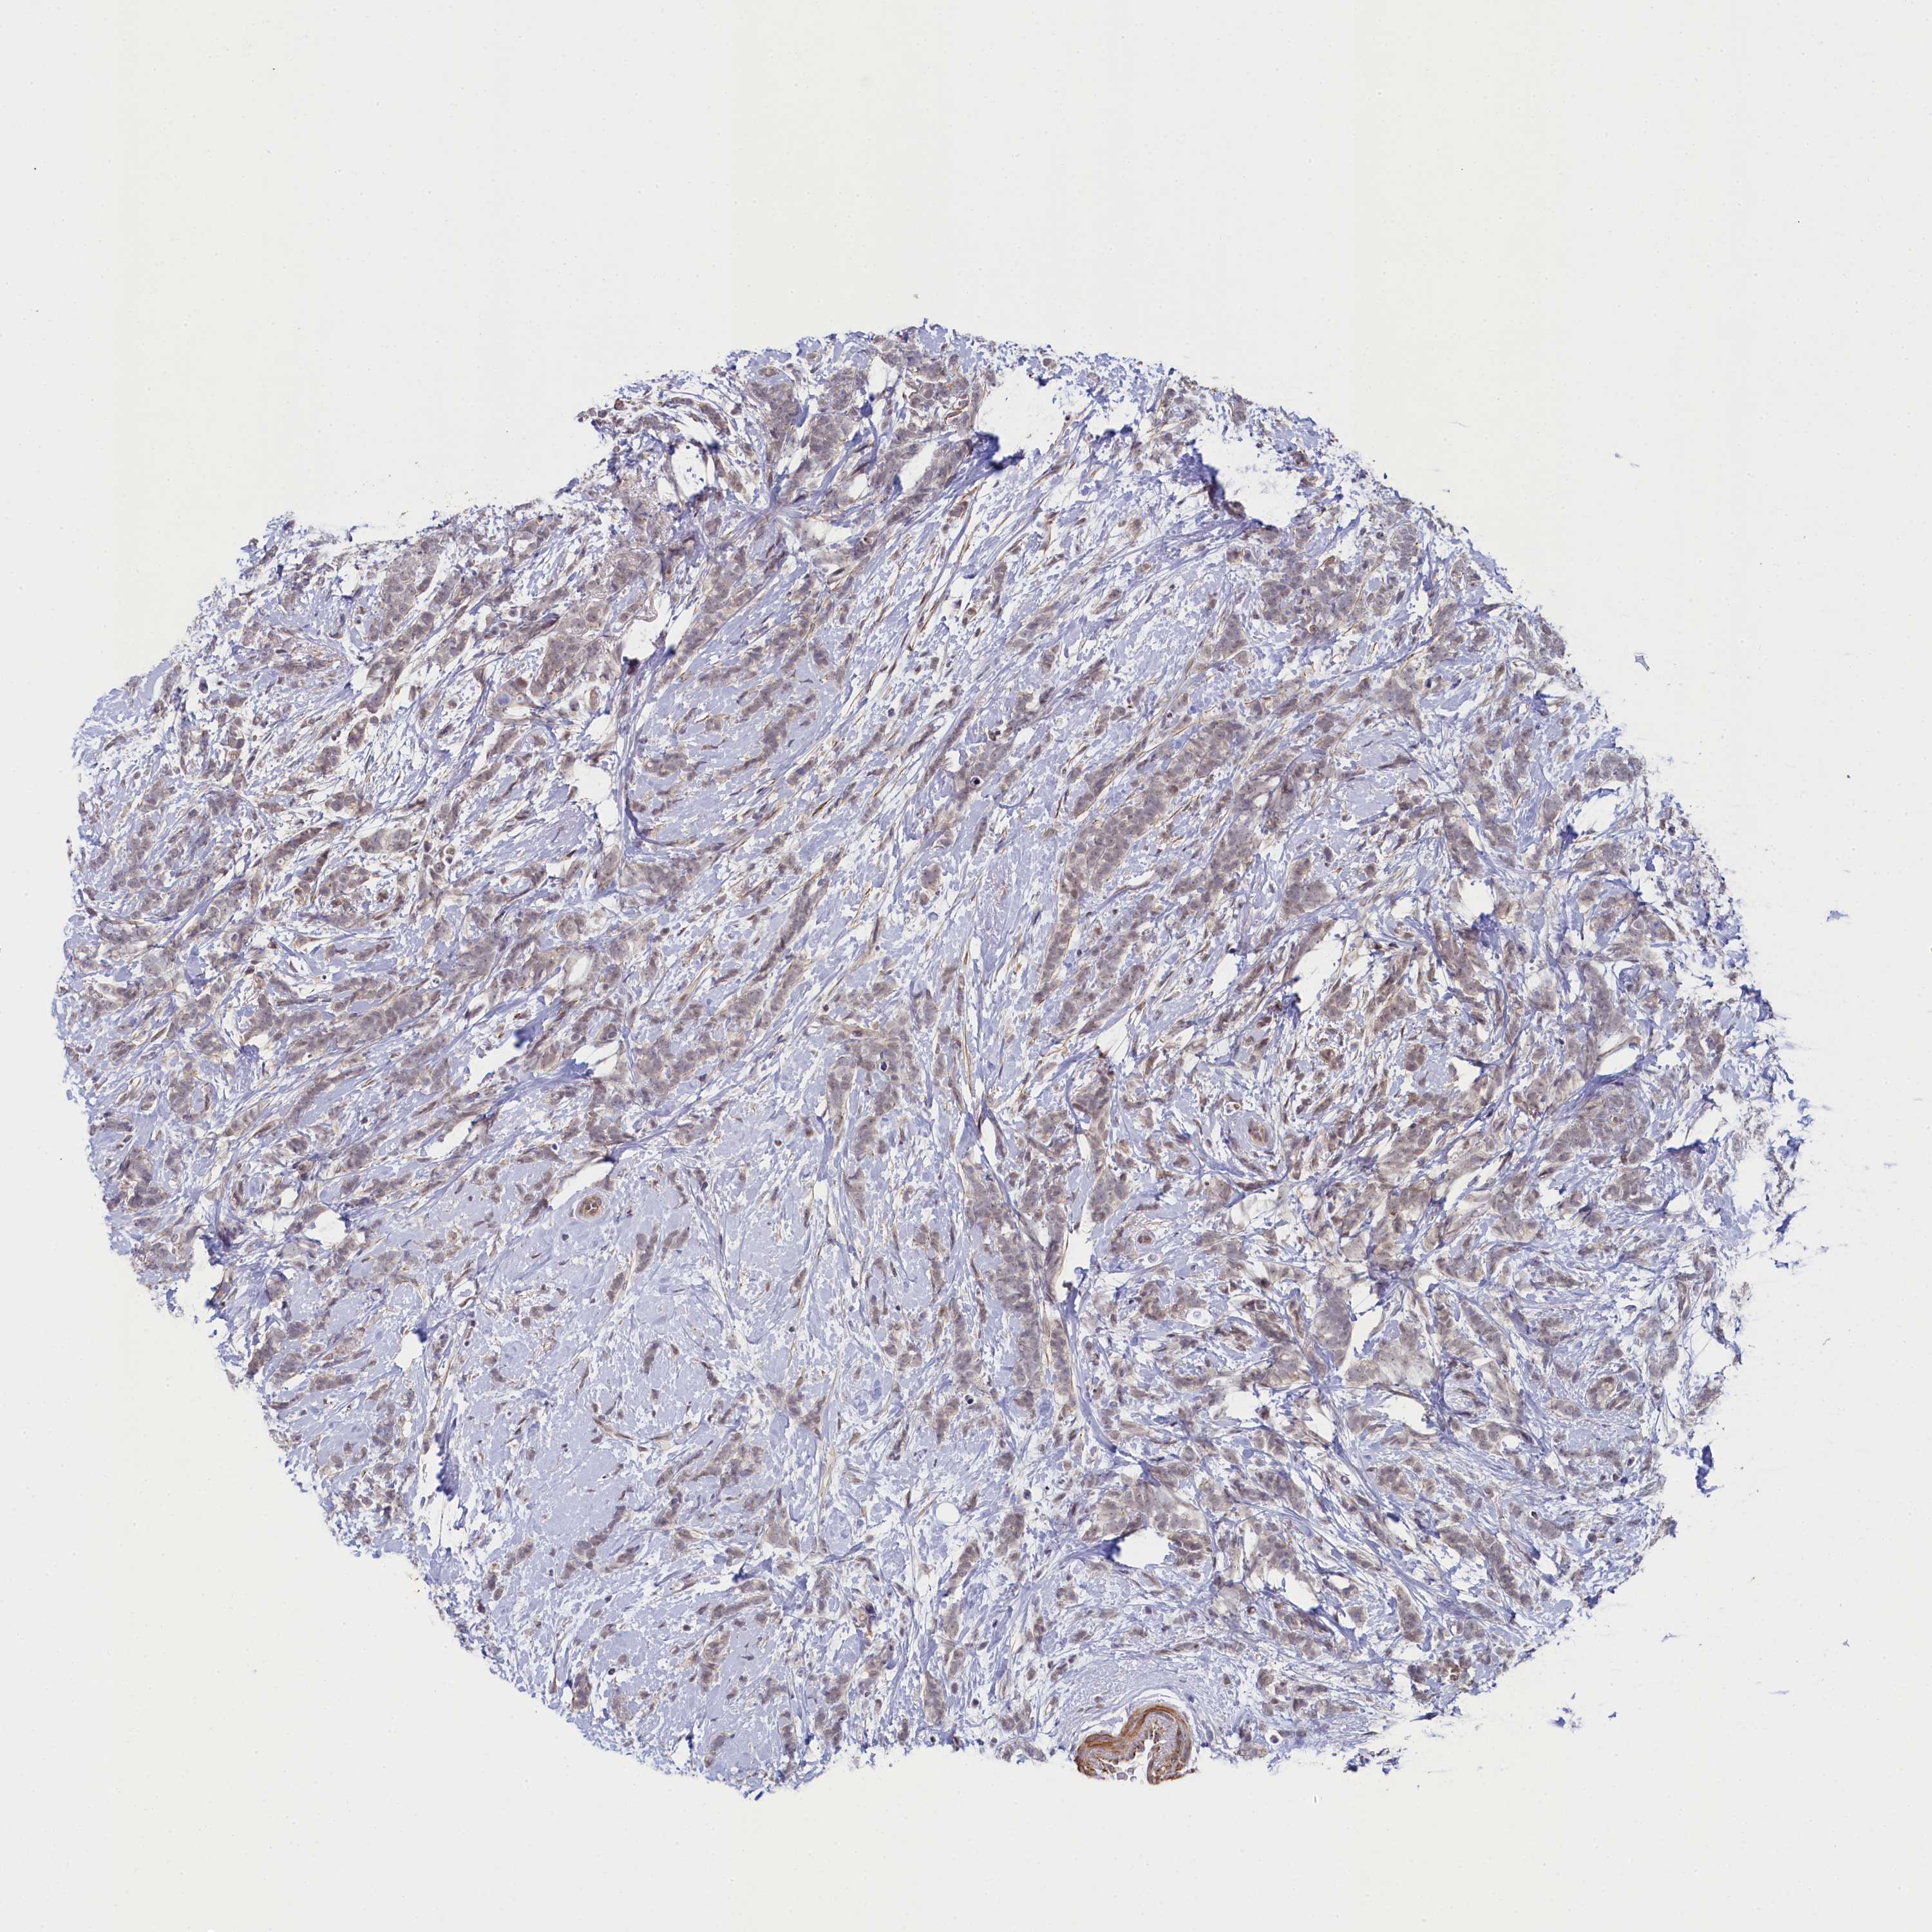

CANCER BREAST CANCER Show tissue menu

BRCA TCGA BRCA VALIDATION PROTEIN EXPRESSION